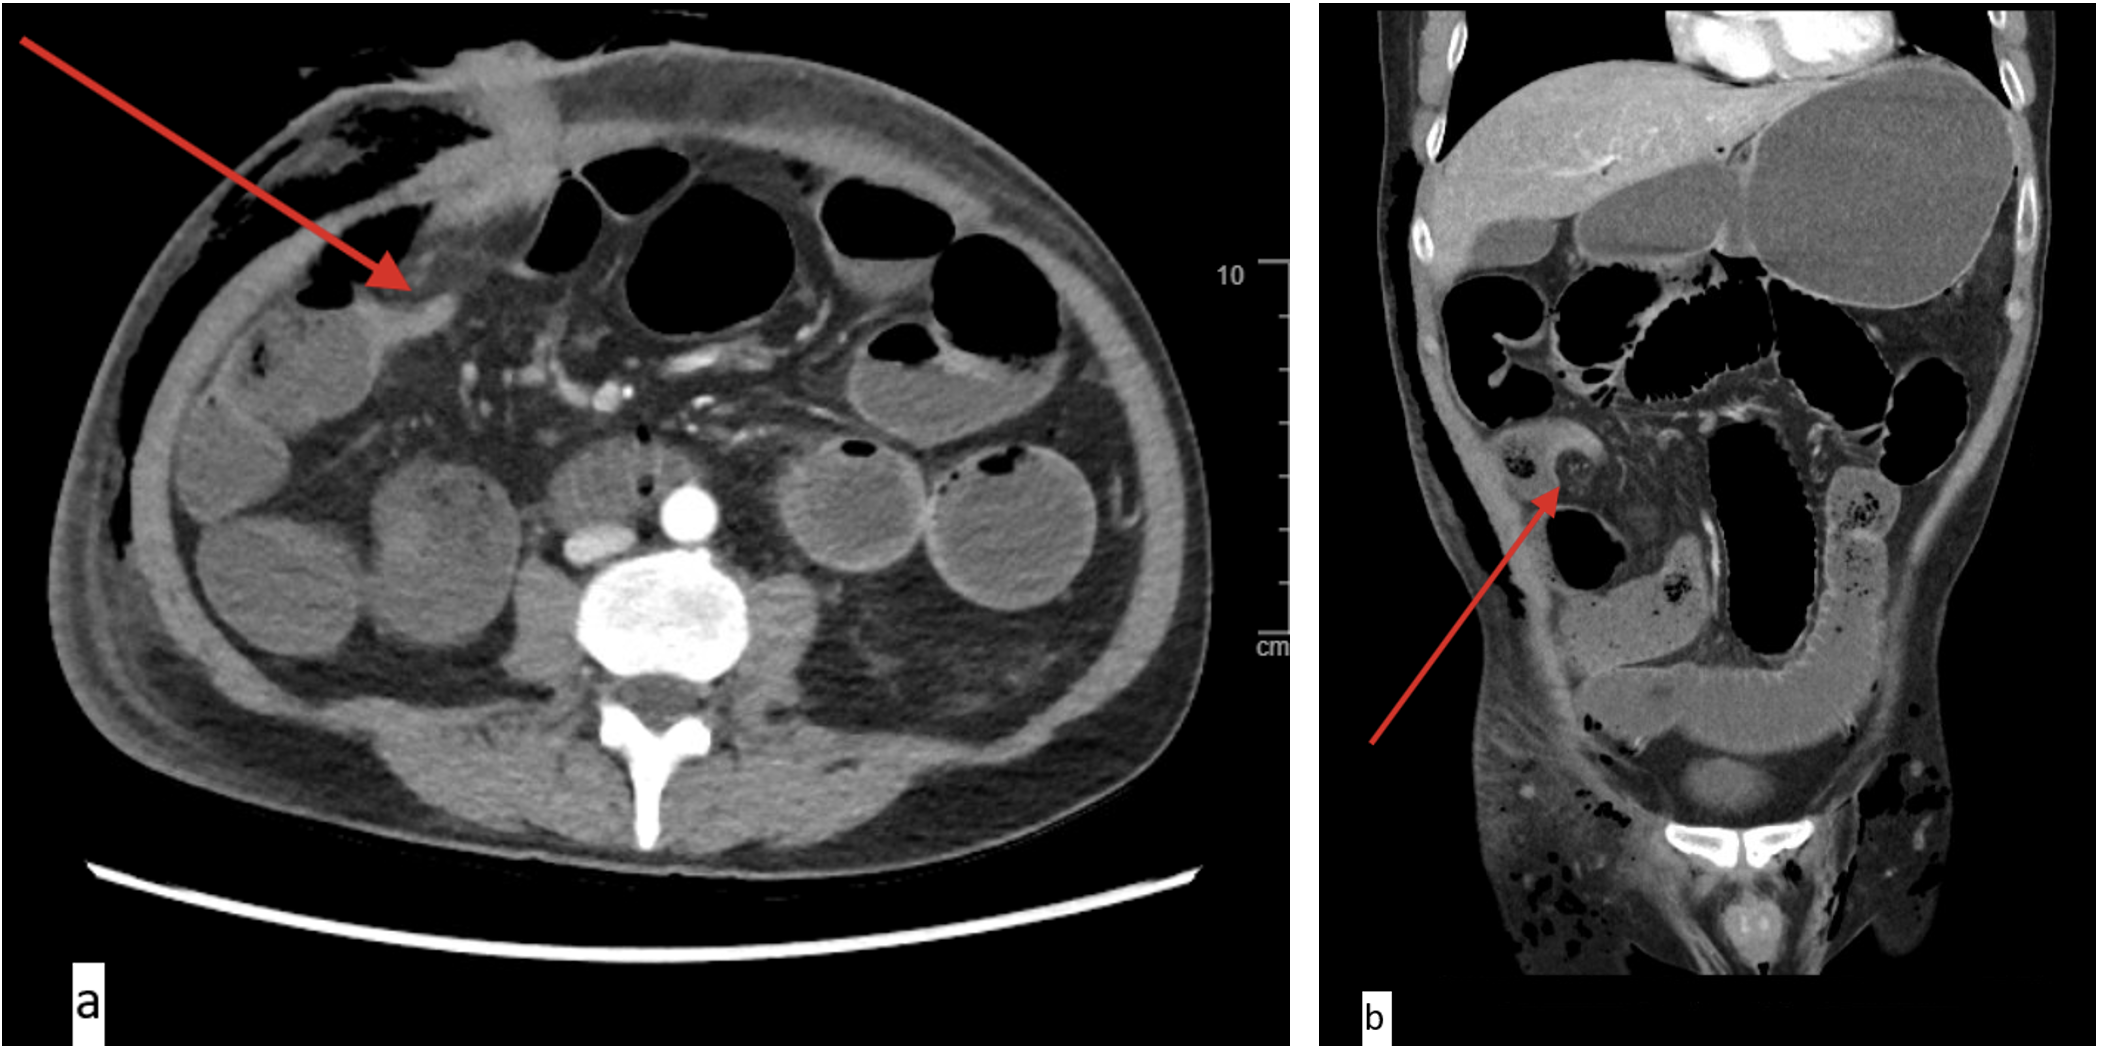

Case One CT Scans

a) Axial imaging depicting transition point at the level of the right upper quadrant ostomy (arrow)

a) Axial imaging depicting transition point at the level of the right upper quadrant ostomy (arrow) b) Coronal imaging depicting mesenteric swirl at the transition point (arrow)